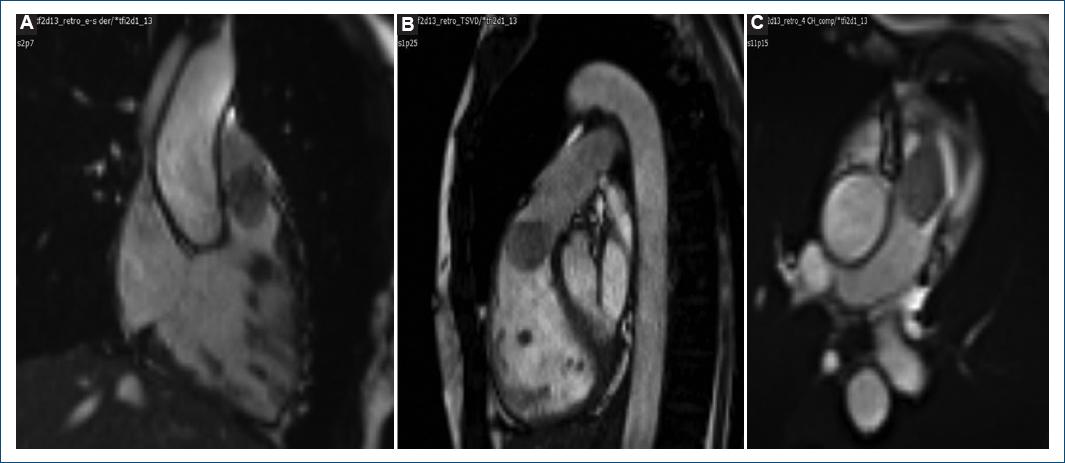

Figure 2 Cardiac magnetic resonance. CMR shows a well-defined, pedunculated mass, arising from de RVOT, occupying 80% of the RVOT (36 × 32 × 20 mm), isointense on T1-weighted images. RVOT: right ventricular outflow tract.

Figure 3 Cardiac magnetic resonance. CMR SSFP cine images. A-C: a well-defined, pedunculated mass, arising from de RVOT, occupying 80% of the RVOT, in contact with the inferior surface of the pulmonary valve. During images in systole, the mass moves through de valvular plane. RVOT: right ventricular outflow tract.